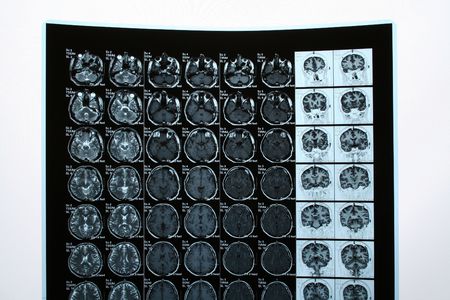

Brain Scan

Series of images from a tomography of the brain

closeup series of MRI images of head and brain, magnetic resonance imaging scan, world cancer day concept

CT Scan brain Finding isodense mass with ill-defined margin and surrounding edema at the Left frontal lobe. Glioblastoma, brain metastasis. Blurry operating room background.

A brain scan is shown on a screen while a patient undergoes a medical imaging procedure.